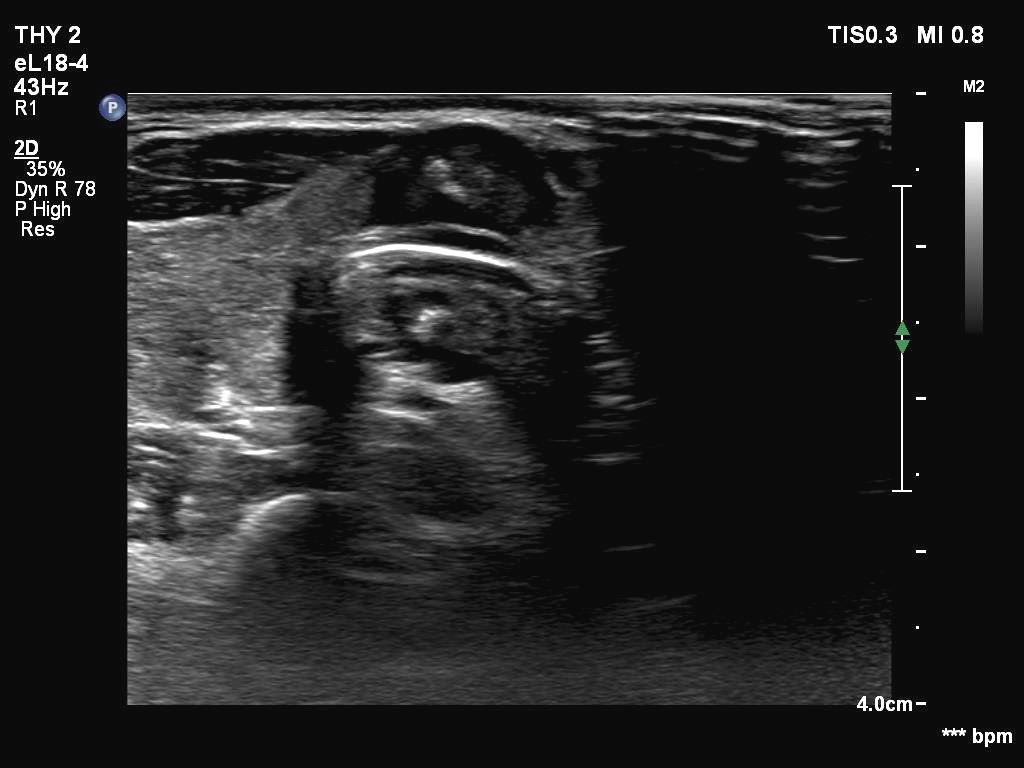

Ultrasonography. The thyroid was echonormal. There were two partly deeply hypoechoic nodules, one in the ventrolateral part of the right lobe and another one in the isthmus. Both had irregular margins and punctate echogenic foci. There was a mirror image artifact of the lesion in the isthmus.

Both nodules had multiple suspicious features: beside deep hypoechogenicity and irregular borders, microcalcifications should be also considered. The nodule in the right lobe presented also three possible sonographic signs of a possible extrathyroidal spread: the pseudocapsule of the thyroid was not intact, the lesion had both abutting and butting contours.

According to the literature, the mirror image artifact is not an exceptional finding. Nevertheless, such a reflection very similar to the original is quite rare. The prerequisite of this phenomenon is the flattening of the trachea' wall as is observed in this case. The explanation is as follows: 'The primary beam reflects from such a surface (e.g. diaphragm) but instead of directly being received by the transducer, it encounters another structure (e.g. a nodular lesion) in its path and is reflected back to the highly reflective surface (e.g. diaphragm). It then again reflects back towards the transducer.' (Source: radiopedia.org.)